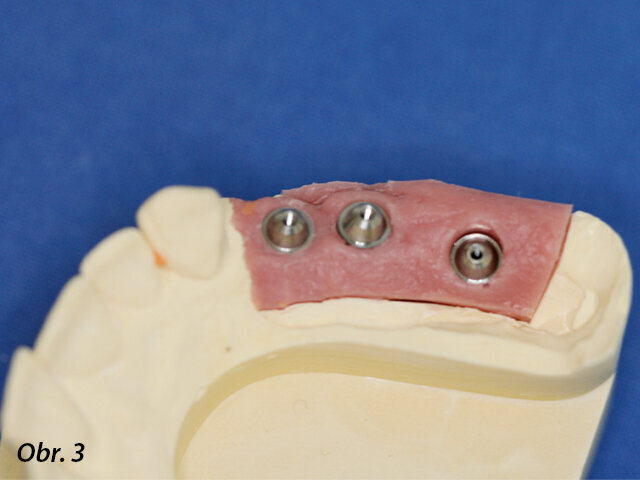

Hlavní model, na kterém je vrchol fixtury zygomatického implantátu umístěn do oblasti palatinálního kořene prvního moláru.